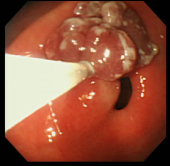

| 切除した部分をクリップで止血 | ポリープ切除した部分の1ヶ月後の粘膜 | ||